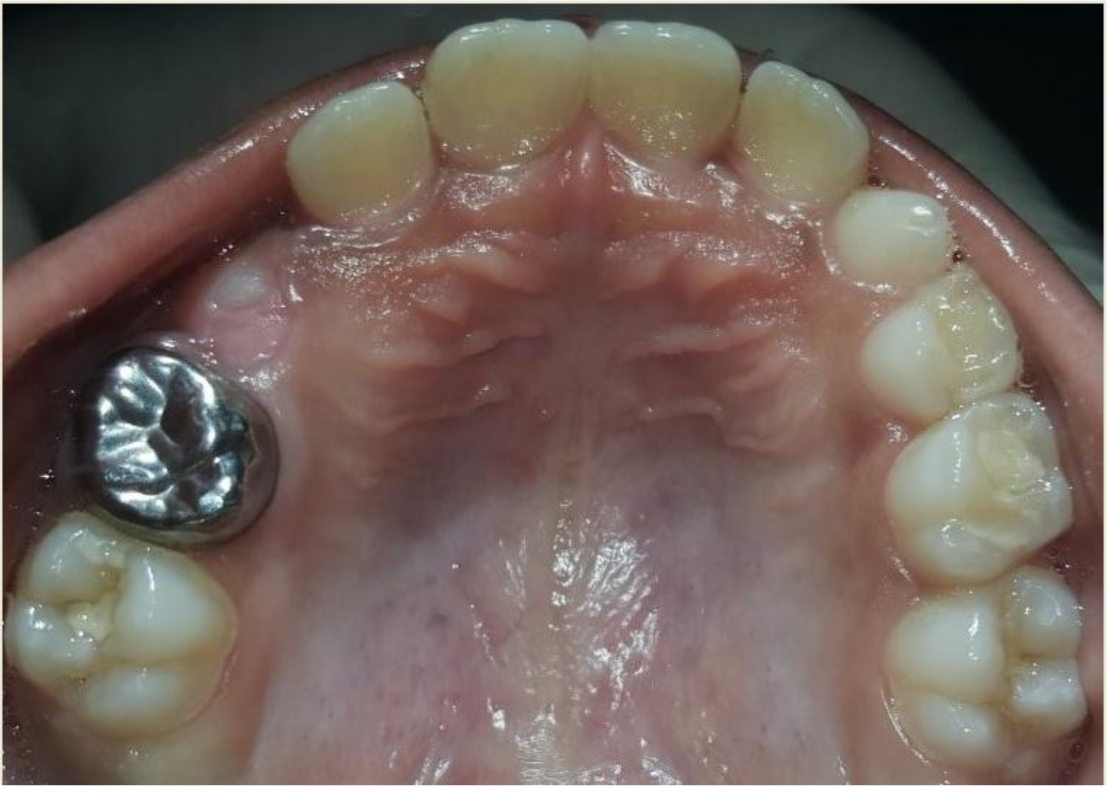

A nine year old boy reported to the Department of Pedodontics and Preventive Dentistry of Bharati Vidyapeeth Deemed University, Sangli with a chief complaint of pain and abscess in the lower left back region of the jaw since one month. Patient was a known case of autism spectrum disorder. He was inattentive, hyperactive and showed repetition of gestures. Psychological testing report showed childhood autism rating scale (CARS) 2, which falls into mild to moderate autistic category. Vineland social maturity scale (VSMS) measuring the social intelligence of child was found to be 31.5 with social age of around 5-6years. The family history was non-contributory. He was not on any medications and had reported no history of drug allergies. Extra-oral examination showed no specific findings (Figure 1). Intraoral examination revealed multiple carious lesions (Figure 2) (Figure 3). Occlusal caries involving enamel, dentin and pulp with 55 and 75. Intra oral dentoalveolar abscess was also seen in relation with 75 (Figure 4). Dentinal caries was seen with 85 and occlusal pit and fissure caries was seen with 65. No soft tissue abnormalities were appreciated. Radiographic evaluation by orthopantomogram was also done which revealed no abnormality (Figure 5). It was difficult for the patient to co-operate on the dental chair and understand the instructions given to him; hence treatment was planned under general anaesthesia. A complete pre anaesthetic evaluation was done and the patient was categorized under ASA II. Treatment plan was explained to the child’s parents and a written consent was obtained from them. The dental treatment done under general anaesthesia included pulpectomy of 55, 75 with glass ionomer cement restoration followed by placement of pre trimmed and pre contoured stainless steel crowns (Figure 6) (Figure 7). Glass ionomer cement restorations were done in 65 and 85 and pit and fissure sealants application on 16, 26, 36 and 46. Post-operative orthopantomogram showed well placed restorations and crowns (Figure 8). Patient’s post-operative recovery was uneventful. Treatment rendered reduced the pain and discomfort.Oral hygiene care instructions were given to the parents and maintenance protocol was explained and they were also encouraged for regular follow-up for preventive dental care. The two months follow-up revealed improved eating habits of the child.

Figure 2 Intra oral pre-operative image of the maxilla.

Figure 6 Stainless steel crown cemented on 55 and glass ionomer cement restoration on 65 and sealants on 16, 26.